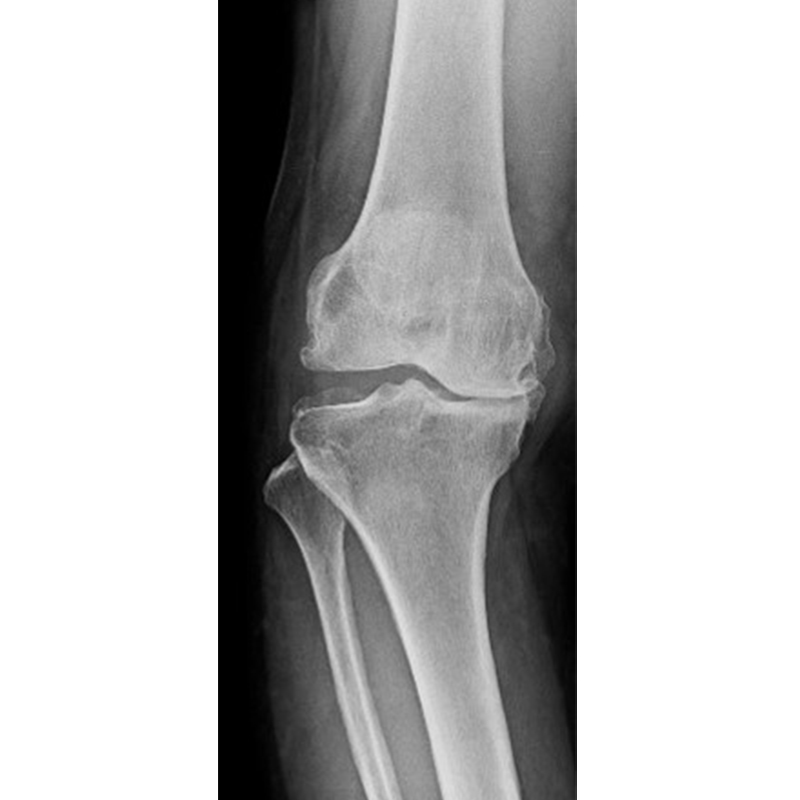

傳統全膝關節置換 首頁 案例分享 膝關節手術 傳統全膝關節置換 江女士 61歲 術前 術後 劉先生 83歲 術前 術後 70歲 柯先生 術前 術後 75歲 黃女士 術前 術後 77歲 羅女士 術前 術後